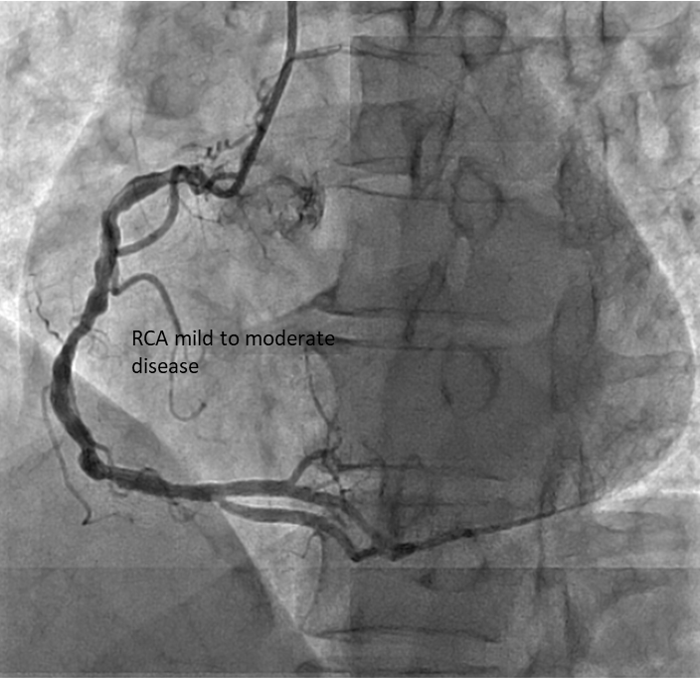

Diagnostic CAG:Left main stem: normalLeft anterior descending artery: proximal 30% stenosis, mid myocardial bridging, diagonal branch giving collateral to OM branchLeft circumflex artery: stent in distal LCX with ISR type IV 100% occlusionRight coronary artery: Dominant, mid 40-50% stenosis, PLV branch giving collateral to OM branch